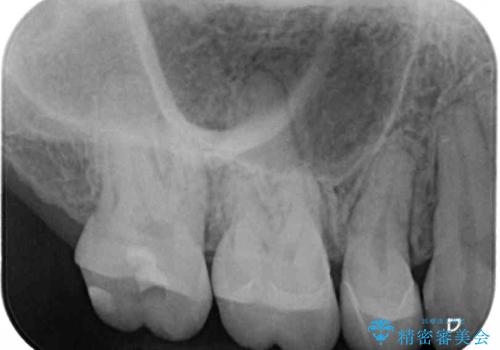

- 他院で抜歯矯正を終えた後、銀色の目立つ奥歯を白くしたいとのことで来院された患者様です。

既にセラミッククラウンが装着されている歯もありますが、不自然な色合いや黒い縁も気になるので、一斉に補綴治療をして統一感を持たせることとしました。

矯正治療を終えたばかりなので、仮歯やセラミッククラウンに置き換えている間に保定がうまくいかなくなる可能性があるため、下顎前歯の舌側を事前にワイヤーで保定しておくこととしました。